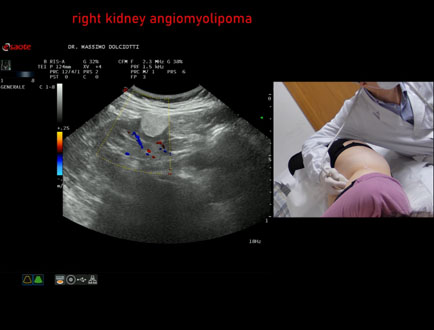

Data inserimento: 03/04/2026

Ecografia del: 12/03/2026

Strumento: Esaote MyLab Eight

Sonda: Convex Multifrequenza 1-8 MHz

Età Paziente: F 66 anni

Motivazione dell'esame: follow up per angiomiolipoma renale destro

Commento all'esame: le immagini ed il video documentano al rene destro, in sede corticale polo inferiore, immagine iperecogena, a margini definiti, delle dimensioni di 25 x 23 mm, senza segni di vascolarizzazione, da ricondurre, come prima ipotesi, ad angiomiolipoma.

Conclusioni: angiomiolipoma del rene destro (angiomyolipoma of the right kidney).

In collaborazione: Dr.ssa Marica Manfredi - Ancona, Dr. Ilir Qose - Ancona

Presentazione: Dr. Massimo Dolciotti - Ancona

Elaborazione digitale: Andrea Dini - Ancona